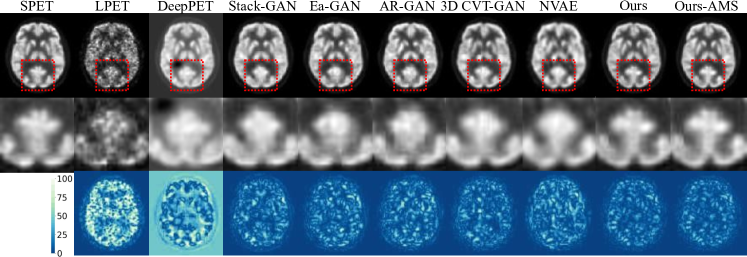

Figure 2: Visual comparison with SOTA methods.

Comparison with SOTA Methods: We compare the performance of our method with 6 SOTA methods, including DeepPET [9] (regression-based method), Stack-GAN [27], Ea-GAN [31], AR-GAN [16], 3D CVT-GAN [32] (GAN-based method) and NVAE [3] (likelihood-based method) on the public dataset. Since the IRM contains a stochastic process, we can also average multiple sampled (AMS) results to obtain a more stable reconstruction, which is denoted as Ours-AMS. Results are provided in Table 1. As can be seen, our method significantly outperforms all other methods in terms of PSNR, SSIM, and NMSE, and the performance can be further amplified by averaging multiple samples. Specifically, compared with the current SOTA method 3D CVT-GAN, our method (or ours-AMS) significantly boosts the performance by 0.558dB (or 0.796dB) in terms PSNR, 0.003 (or 0.004) in terms of SSIM, and 0.006 (or 0.007) in terms of NMSE. Moreover, 3D CVT-GAN uses 3D PET images as input. Since 3D PET images contain much more information than 2D PET images, our method has greater potential for improvement when using 3D PET images as input. Visualization results are illustrated in Figure 2. Columns from left to right show the SPET, LPET, and RPET results output by different methods. Rows from top to bottom display the reconstructed results, zoom-in details, and error maps. As can be seen, our method generates the lowest error map while the details are well-preserved, consistent with the quantitative results.